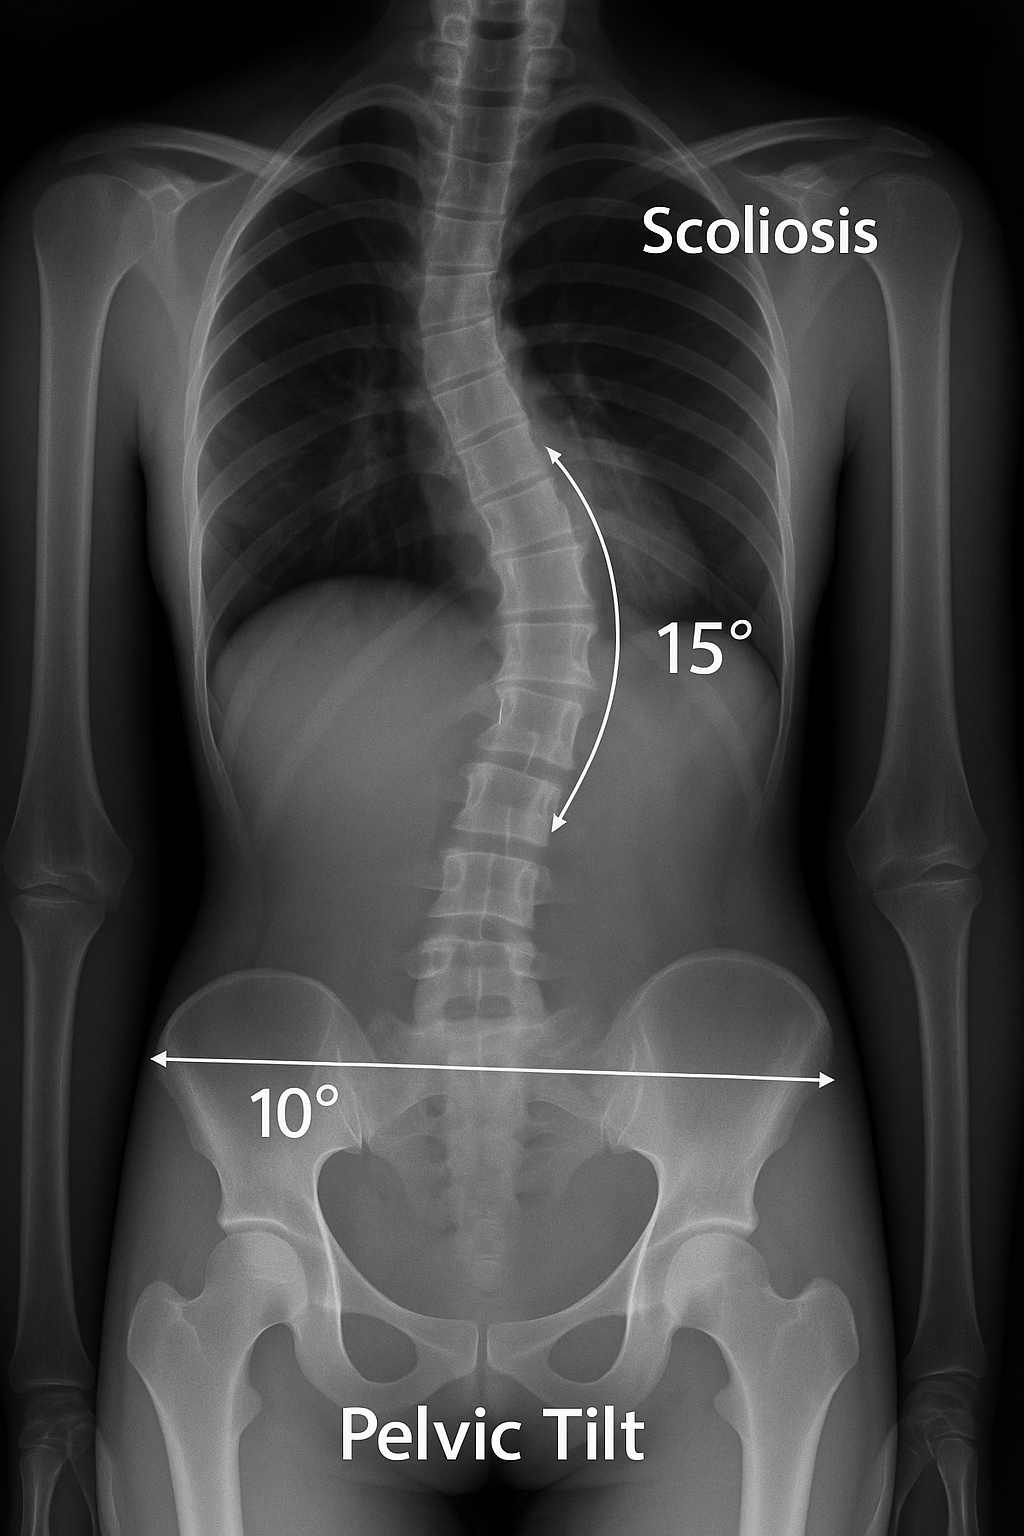

골반은 인체의 기초 구조물로써 척추를 위로 지탱하고 하체와 연결하는 중심적인 역할을 담당합니다. 따라서 골반이 좌우 어느 한쪽으로 기울거나 앞으로 과도하게 경사되면 척추는 그 균형을 맞추기 위해 자연스럽게 변형됩니다. 이를 장기간 방치하면 척추가 C자 또는 S자 형태로 휘어지는 측만증이 발생하거나 이미 존재하는 측만증이 더욱 악화될 수 있습니다. 실제로 정형외과 임상에서도 골반 불균형이 있는 환자의 상당수가 척추 측만증을 동반하고 있다는 보고가 있습니다.

골반 불균형은 크게 좌우 불균형, 전방 경사, 후방 경사로 구분됩니다. 좌우 불균형은 한쪽 골반이 올라가거나 내려간 상태를 의미하며, 이는 다리 길이 차이나 잘못된 앉는 습관에서 비롯됩니다. 전방 경사는 허리가 과도하게 앞으로 꺾이면서 골반이 앞으로 기울어진 상태로, 장시간 앉아 있는 현대인에게 흔히 나타납니다. 후방 경사는 반대로 골반이 뒤로 말린 상태로, 허리가 굽어지고 등이 구부정해지는 특징이 있습니다. 이러한 골반 불균형은 척추의 정렬을 깨뜨려 결국 척추 변형을 유발하게 됩니다.

첫째, 골반 불균형은 척추의 기울기를 유발합니다. 골반은 척추의 기초 지반과 같기 때문에, 한쪽이 높거나 낮으면 척추가 그 위에서 기울어지게 됩니다. 이는 마치 건물이 기울어진 땅 위에 세워졌을 때 구조물이 기울어지는 것과 같은 원리입니다. 장기간 반복되면 척추는 자연스러운 만곡을 잃고 측만증으로 발전합니다.

둘째, 골반 불균형은 척추 근육의 좌우 불균형을 심화시킵니다. 한쪽 골반이 올라간 상태에서는 반대쪽 허리 근육이 늘어나 약해지고, 올라간 쪽의 근육은 단축되어 뭉치게 됩니다. 이로 인해 척추가 한쪽으로 끌려가면서 만곡이 심화되고, 통증과 피로감이 동반됩니다. 실제로 측만증 환자들은 척추만 변형된 것이 아니라 골반과 하체 근육에도 뚜렷한 불균형이 나타납니다.

셋째, 골반 불균형은 보행 패턴에도 영향을 줍니다. 골반이 틀어진 상태에서 걷게 되면 양쪽 다리에 실리는 체중이 달라지고, 보행 시 척추에 반복적인 충격이 가해집니다. 이는 척추의 휘어짐을 악화시키는 요인으로 작용하며, 시간이 지날수록 체형 불균형이 고착화됩니다.